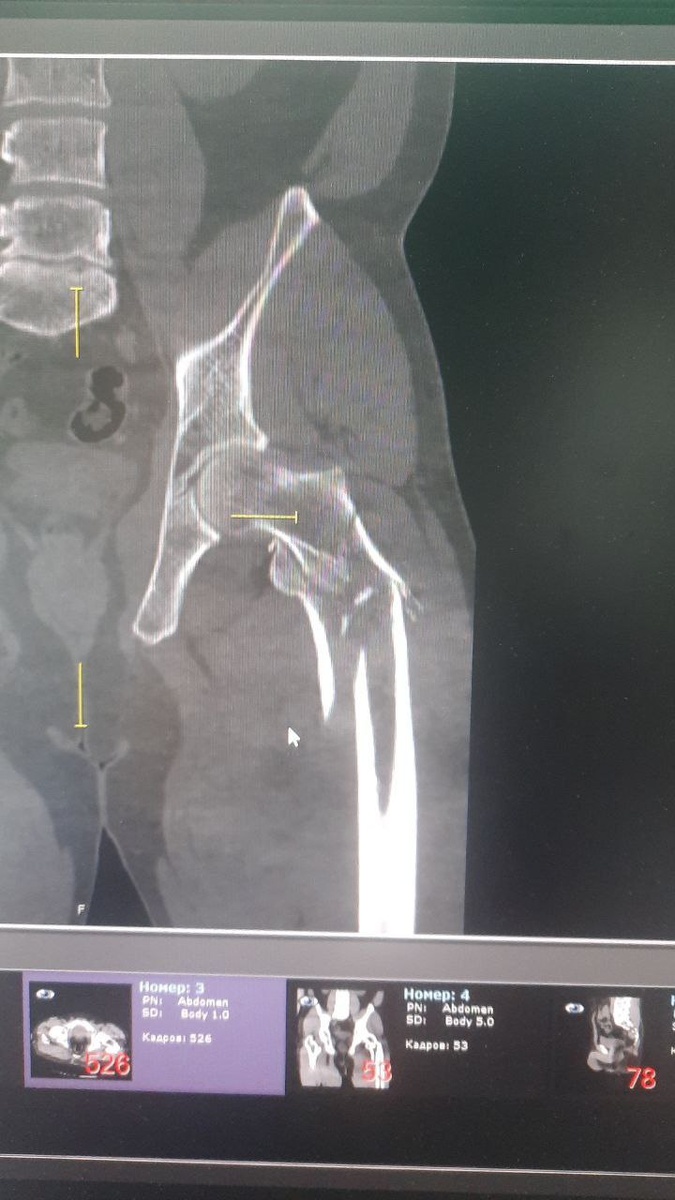

😨 В результате аварии водитель мотоцикла, Алексей, получил серьёзные повреждения и был госпитализирован в местную больницу бригадой скорой помощи в тяжёлом состоянии, с большой кровопотерей. Врачи диагностировали тяжёлую сочетанную травму рёбер с обеих сторон, ушиб лёгкого, вывих предплечья справа с переломом локтевого отростка, переломом лучевой кости, вывихом локтевой кости в лучезапястном суставе, а также многооскольчатые переломы бёдер и голени.

😎Лечащий врач пациента, травматолог-ортопед Павел Гулаков и его коллеги одну за другой выполнили три операции: сначала стабилизировали правую ногу, которая наиболее сильно пострадала при ДТП, затем прооперировали левую ногу и правую руку. Все вмешательства прошли успешно.